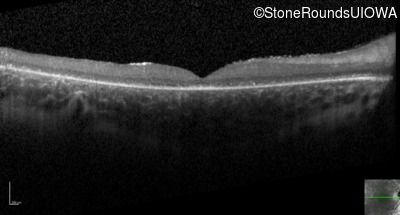

Optical Coherence Tomography - Right - 20/200 sc

Exemplar / OCT Stack